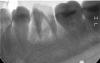

romali83 Опубликовано 17 мая, 2013 Поделиться Опубликовано 17 мая, 2013 Очень нужен совет. Поломан 36 зуб. Поломан давно. Сказали пульпит и воспаление, зуб нужно удалять и ставить мост. Мост не хочется, хочется спасти зуб любой ценой, был бы смысл. Не очень доверяю нашим врачам, т.к. однажды по похожим показаниям уже зуб удалили, а после другой врач сказал, что зуб запросто можно было спасти, но нужно было поработать. Поэтому очень хотелось бы знать, действительно ли уже никак нельзя спасти зуб? Хотя бы под дальнейшее протезирование. Ссылка на комментарий

Alisa st Опубликовано 18 мая, 2013 Поделиться Опубликовано 18 мая, 2013 У Вас снимок очень плохого качества, по нему вообще ничего нельзя сказать. Ссылка на комментарий